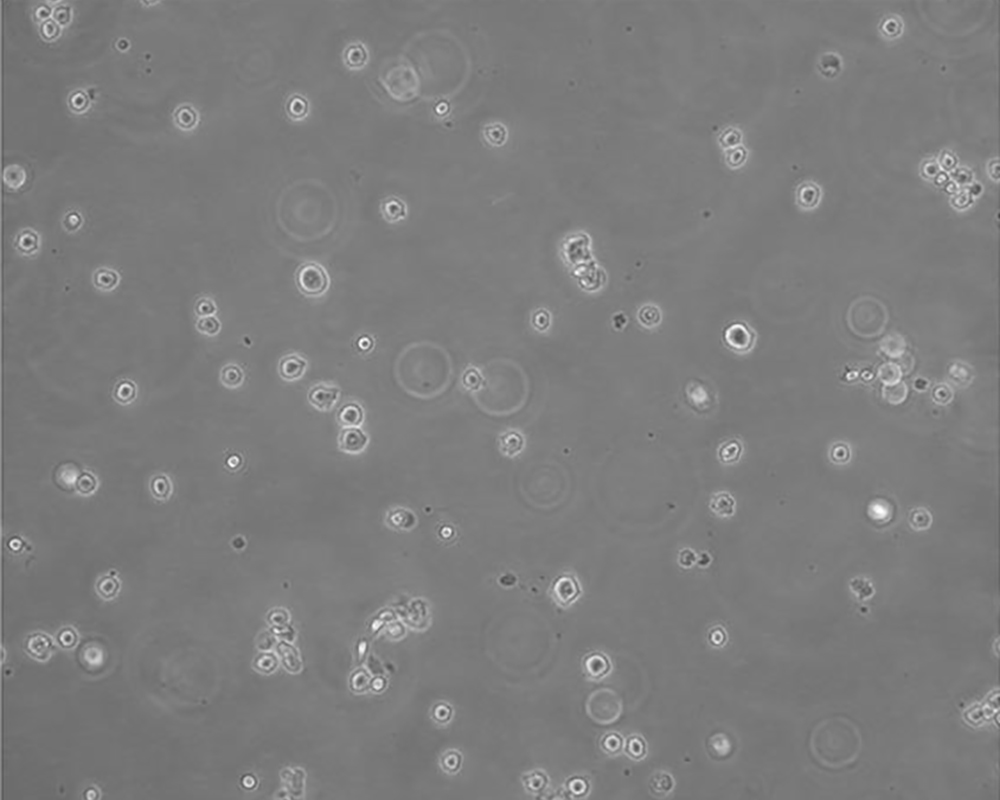

生長(zhǎng)特性 suspension

形態(tài)特征 lymphoblast

細(xì)胞描述 該細(xì)胞來源于多發(fā)性骨髓瘤男性患者,表達(dá)IgG,分泌IL-6。